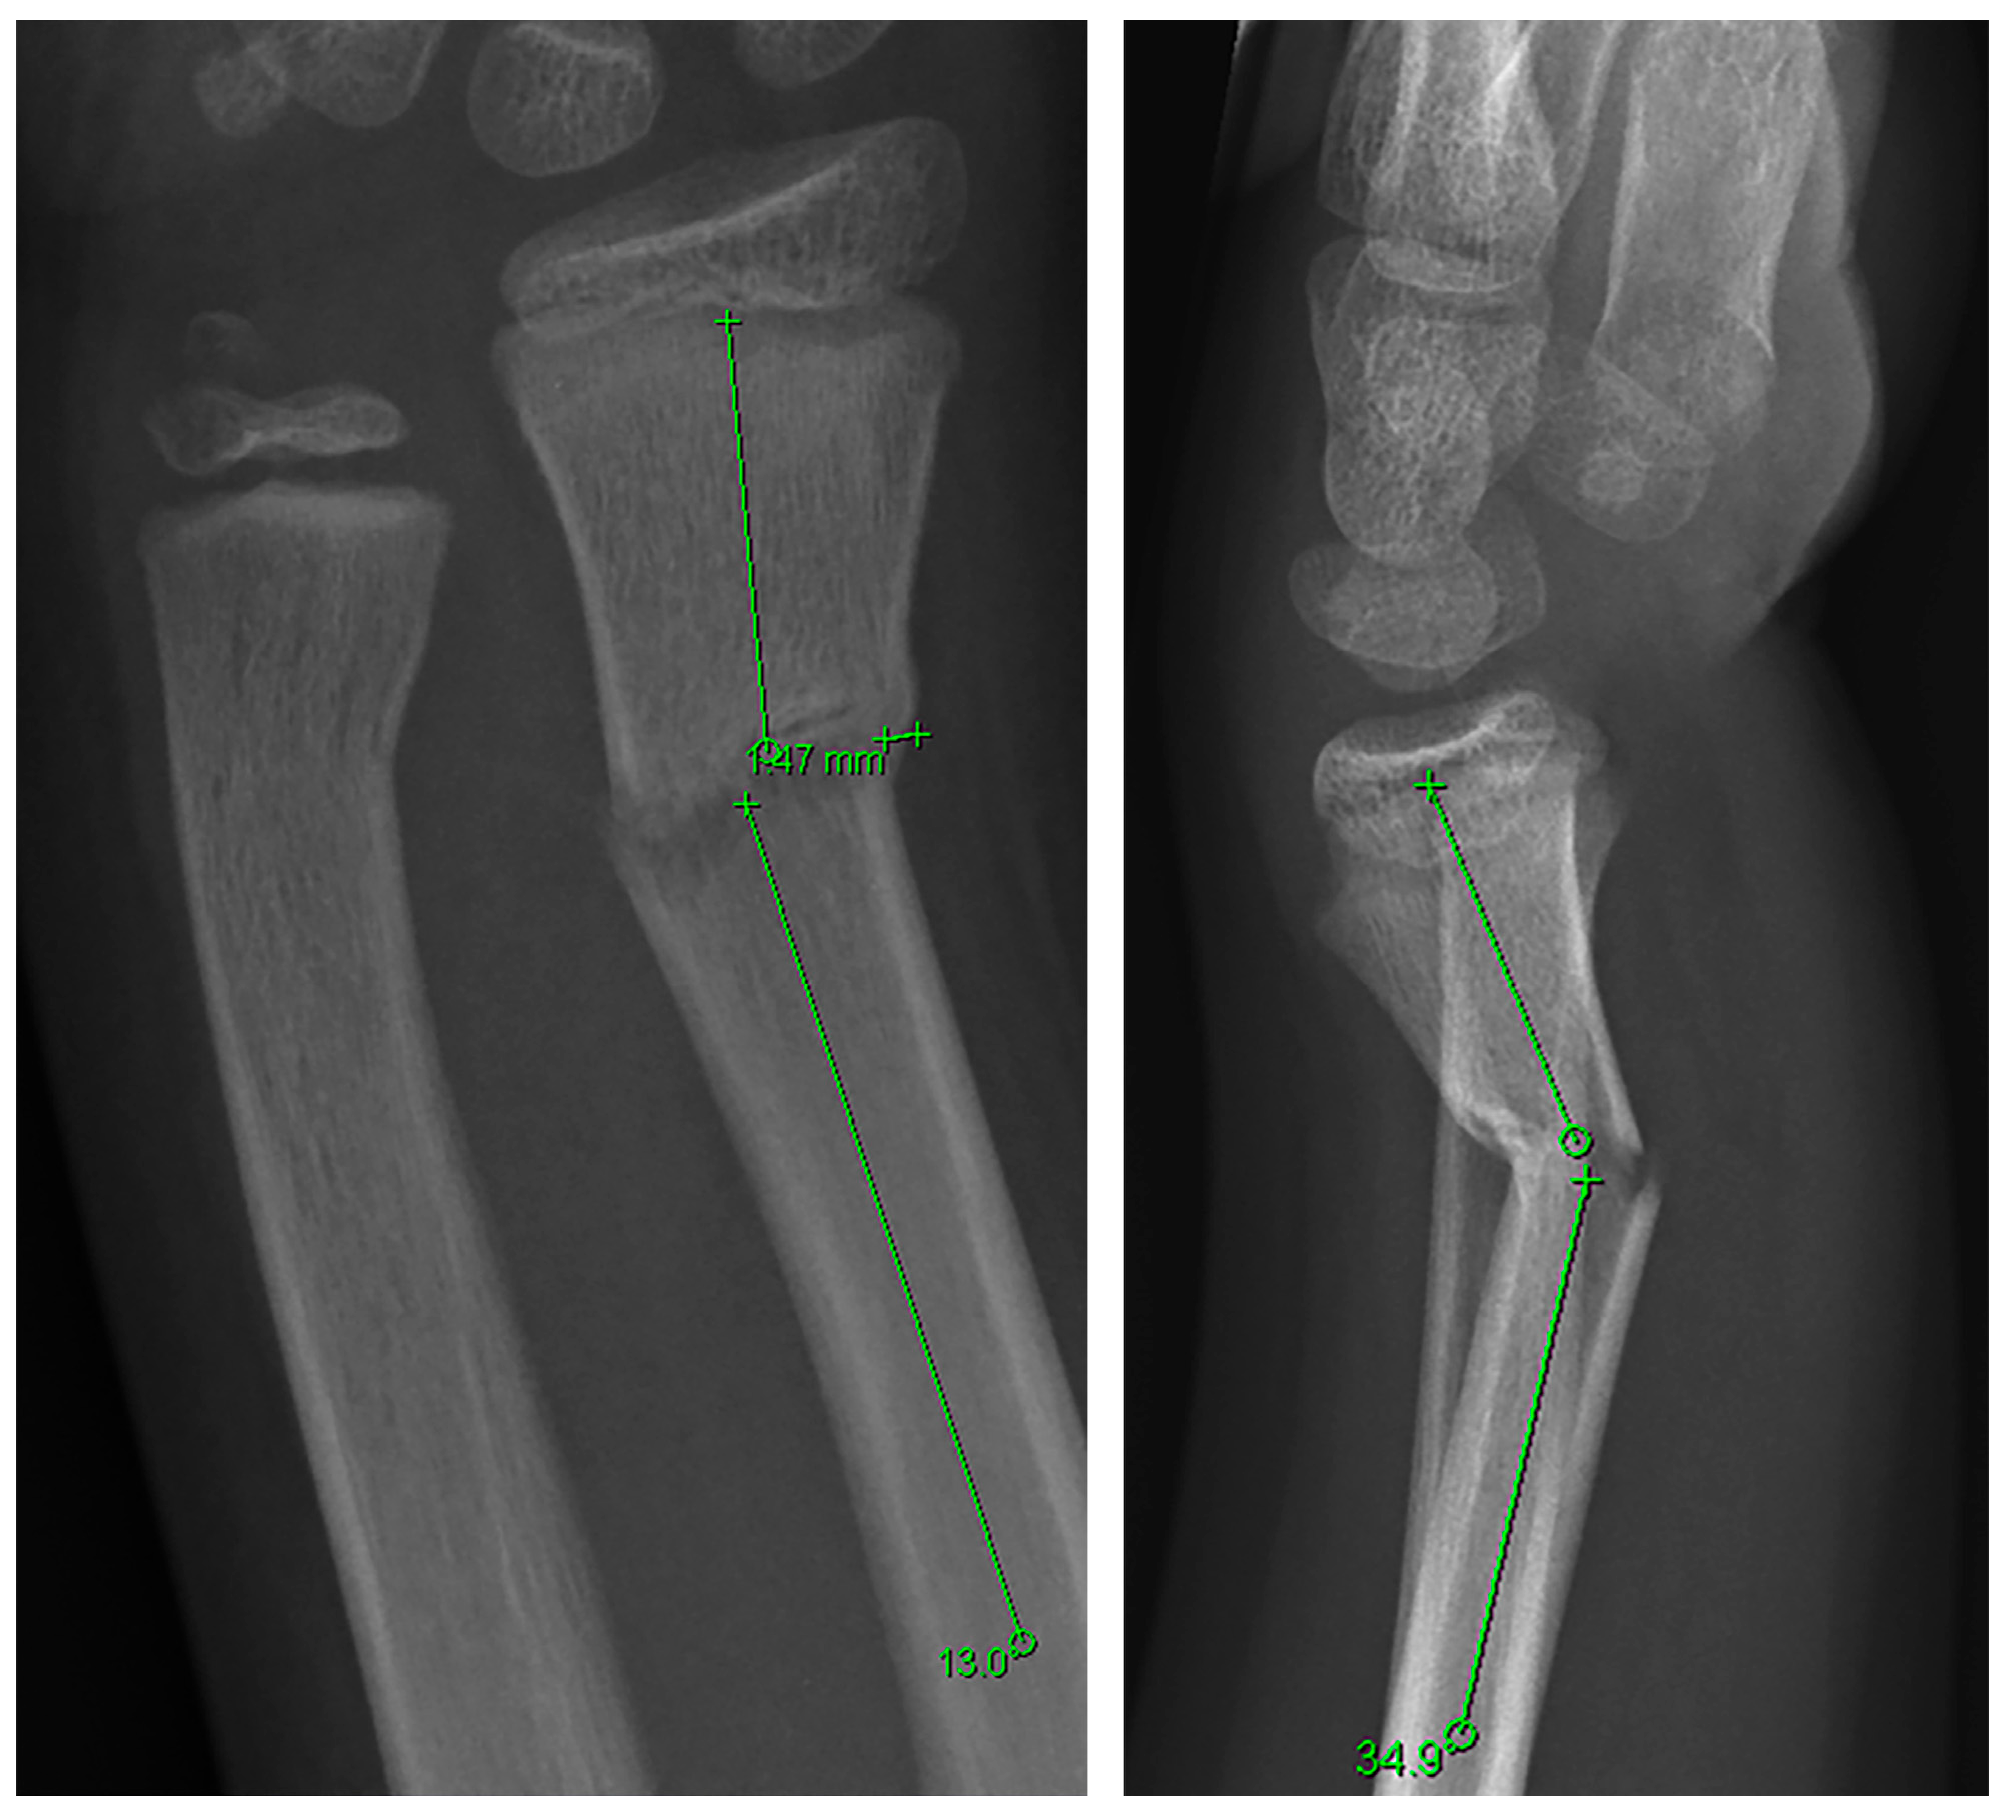

3.1. Participants, Fracture Characteristics and Treatment

3.1.1. Distal Metaphyseal Fractures

3.1.2. Diaphyseal Fractures